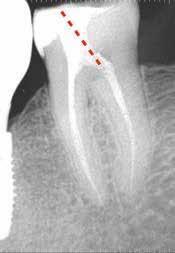

CÉLZOTT ENDODONCIAI MIKROSEBÉSZET

1. a-n. ábrák: Preoperatív CBCT-felvétel a bal alsó 6-os (3.6) fogról. Az axialis (a), coronalis (b) és sagittalis (c) nézeteken a mezialis és distalis gyökerek apicalis harmada körül sugáráteresztő zóna és ép buccalis corticalis csont látható. Egy olyan sablont terveztünk, amely jelezte a csontablak határait az apicalis terület pontos elérése érdekében (d). A mikrosebészeti bevatkozás során a sablont a helyére illesztettük (e), a csontablak határait megjelöltük (f) egy Piezotome CUBE LED kézi-darabba fogott fűrésszel, majd kivágtuk és eltávolítottuk (g és h) az apicalis területhez történő hozzáférés, illetve a mezialis és distalis gyökerek rezekciójának, retrográd preparációjának és retrográd gyökértömésének elvégzése érdekében (i). Végezetül a csontablakot visszaillesztettük és kollagén szivaccsal stabilizáltuk (j). A műtét után közvetlenül készített röntgenfelvétel a 3.6-os fogról (k). A kétéves kontroll során készített CBCT-felvétel: axialis (l), coronalis (m) és sagittalis (n) nézetek.

Egy 63 éves páciens korábban már kezelt bal alsó első nagyőrlőfogából (3.6) eredő mérsékelt fájdalom miatt kereste fel rendelőnket. A kórtörténetében panasza szempontjából releváns információ nem szerepelt. Az elkészült CBCT-felvételen a korábbi kezelések során észre nem vett, jelenleg feltáratlan meziobuccalis csatornát, valamint a mezialis és distalis gyökerek körül kialakult periapicalis elváltozást, és ezt a léziót borító intakt buccalis corticalis csontlemezt láttunk.

Klinikai vizsgálat során vertikális kopogtatási érzékenységet jelzett. A fog körül mérhető szondázási mélység és a fogmobilitás fiziológiás volt. A CBCT-felvételen nem észleltünk a csontos regeneráció megindulására utaló jeleket (1. a–c. ábrák). A korábban gyökérkezelt, gyökértömött és revideált 3.6-os fog esetében az alábbi diagnózis került felállításra: periodontitis periapicalis symptomatica. A panaszokat okozó fog további ellátása során navigált endodonciai mikrosebészetet kívántunk alkalmazni. Az alsó állcsontról intraorális szkent (TRIOS, 3Shape) készítettünk, és a felszíni topográfiát tartalmazó STL fájlt, valamint a CBCT-felvétel készítése során nyert DICOM fájlokat a Blue Sky Bio szoftver segítségével egyesítettük. A sebészi sablon megtervezésére az így kapott háromdimenziós képet használtuk. A sablon kialakítása során arra törekedtünk, hogy a sablon egyértelműen meghatározza a gyökércsúcsi terület eléréséhez szükséges csontablak határait (1. d. ábra)